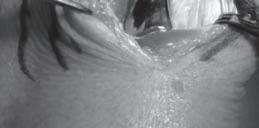

Blok nervus medianus – Blokáda nervus medianus poskytne anestezii palmární části palce, ukazováku, prostředníku a radiální poloviny prsteníku, blokovány jsou také flexory předloktí a zápěstí, svaly tenaru a periost obou kostí předloktí volárně. Místo vpichu v úrovni lokte leží těsně mediálně od brachiální tepny (obr. 2.4), po stimulaci nervu aplikujeme 5 ml anestetika. V úrovni zápěstí nerv blokujeme mezi šlachami musculus flexor carpi radialis a musculus flexor palmaris longus (obr. 2.5). Při průchodu jehly přes retinaculum flexorum aplikujeme 2‒4 ml lokálního anestetika.

Blok nervus radialis – Po blokádě nervus radialis dochází k anestezii late-

rální části dorza ruky a palce, proximálních částí palce, ukazováku a prostředníku a radiální poloviny prsteníku. Blokován je také musculus flexor pollicis brevis. Místo vpichu v úrovni lokte leží 2 cm laterálně od šlachy bicepsu na spojnici obou epikondylů (viz obr. 2.4). Po negativní aspiraci aplikujeme 5 ml roztoku lokálního anestetika. V úrovni zápěstí aplikujeme 3 ml anestetika vějířovitě do podkoží podél šlachy musculus extensor pollicis longus a do fossa tabatière.

Blok nervus ulnaris – Blokáda nervus ulnaris poskytne anestezii ulnární hrany ruky, malíku a prsteníku. Blokovány jsou také všechny malé svaly ruky kromě musculi lumbricales prvního a druhého prstu a svalů tenaru. Blok v lokti zásadně neprovádíme při jeho průběhu v sulcus nervi ulnaris, ale asi 3 cm nad ním (viz obr. 2.4). Do podkoží a k pažní kosti aplikujeme vějířovitým způsobem 5 ml roztoku lokálního anestetika. Ulnární nerv v úrovni zápěstí blokujeme pod šlachou musculus flexor carpi ulnaris mezi ulnární tepnou a os pisiforme (viz obr. 2.5).

Obr. 2.4 Blokády koncových nervů v úrovni lokte

Obr. 2.5 Blokády koncových nervů v úrovni zápěstí